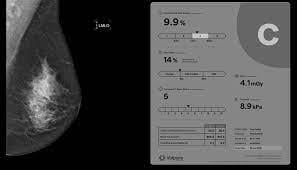

The prestigious Joint AAPM Task Group 282/EFOMP Working Group, focused on modernizing breast radiation dose modeling, recently published a report outlining their new model in Medical Physics. The report, "Breast dosimetry for standard and contrast-enhanced mammography and breast tomosynthesis," advocates for international harmonization of mammography dose estimates, by implementation of the new and improved model and methodology. The new model replaces assumptions of a homogeneous breast with a more representative fibroglandular tissue distribution and shifts to the use of percentage volumetric breast density (%VBD) to align with a clinically implemented breast composition metric. Volumetric breast density emerges as an essential input to facilitate patient-based radiation dose estimates. Volpara's TruDensity algorithm provides reliable estimates of %VBD from 2D and 3D images across multiple mammography system makes and models.

This new dose model will be integrated into Volpara's TruRadDose algorithm, which analyzes a patient's exposure to radiation from a mammogram, with the aim of ensuring patient safety while maintaining optimal image quality.

Featured in European Radiology, a second peer-reviewed study investigates whether active use of Volpara Analytics software could help breast radiographers to improve their screening image quality. The paper "Using automated software evaluation to improve the performance of breast radiographers in tomosynthesis screening," reports on analysis of a quality improvement project where radiographers and researchers from the Breast Radiology Unit at the Veneto Institute of Oncology, encouraged active use of Analytics and led monthly face-to-face coaching sessions with each of six participating radiographers to review individualized feedback based on the objective breast compression and positioning quality metrics measured by Volpara's TruPressure and TruPGMI AI algorithms. All radiographers improved their performance, with increases in quality scores of up to 16% compared to a baseline measurement. The study concluded that employing Volpara's AI-driven software significantly enhances radiographers' performance, thereby improving mammography quality and potentially leading to better screening outcomes for patients. The study's lead author, Gisella Gennaro, notes that a key aspect of the project was to determine whether use of Volpara Analytics software by even the most senior radiographers, would be both accepted and beneficial. She comments that the quality of "all radiographers benefited from the personalized learning experience, with consistent and objective measurements that can be benchmarked against peers."